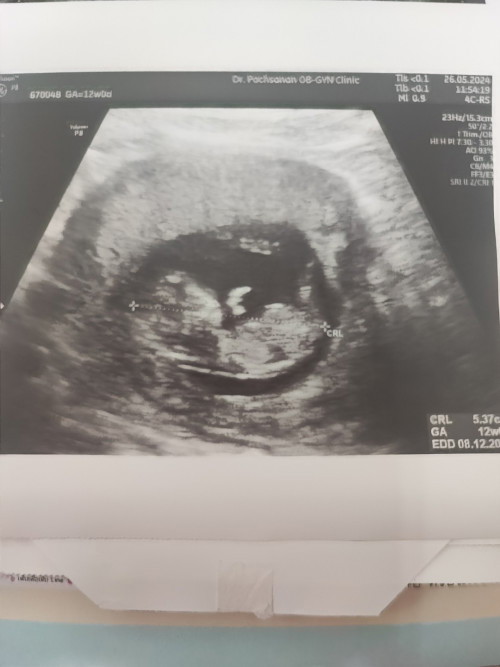

12วิคค่ะ ตอนไปหาหมอดิ้นเยอะมากค่ะ